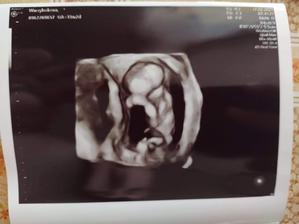

Tehotenstvo #5

Ako rastieme v brušku😘

Ahoj tak dúfam že sa chlapček podaril alebo do 5tice dievčatko...